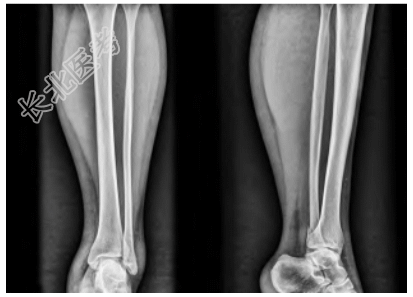

- [材料题] 患者,女,39岁,主诉“外伤致左踝部疼痛、活动受限1h”入院,就诊于日照市中医医院急诊外科。查体:左侧踝关节局部软组织肿胀压痛,后外侧压痛明显,踝关节活动受限,可触及足背动脉搏动,左侧下肢远端血运、感觉、活动未见明显异常。辅助检查:左侧胫腓骨(包括踝关节)X线片显示左侧腓骨远端骨折,骨折块在正位片被腓骨干遮挡(图1)。入院后完善踝关节CT检查,CT横断面显示左侧腓骨远端后侧骨折块,骨折块向胫骨侧移位,骨折线沿冠状面走形,左侧腓骨切迹为Ⅰ型,右侧腓骨切迹为C型(图2);CT矢状面显示左侧腓骨远端后侧骨折块,未累及腓骨干(图3)。CT三维重建显示左侧腓骨远端后侧类椭圆形骨折块,为明确有无下胫腓联合韧带断裂,完善MRI检查,MRI显示下胫腓前、后韧带均完整,下胫腓后韧带与骨折块相连(图4),牵拉骨折块向内侧移位,PDW序列显示下胫腓后韧带存在浅深两层且在部分层面存在融合。以上检查结果可明确诊断下胫腓后韧带腓骨端撕脱骨折。